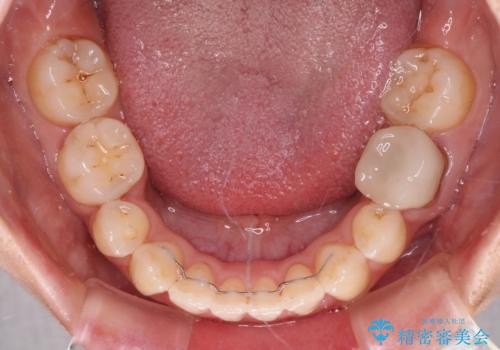

上下の前歯に隙間が空くほど上顎前歯が前に飛び出していましたが、抜歯矯正により上下前歯がぴったりと付くほど口元を引っ込めることができました。

- 矯正治療後の保定が不十分だと後戻り(元の位置に戻ろうとする動き)をします